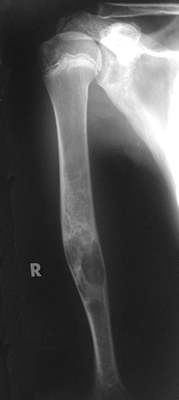

Direkt nach der Metallentfernung sieht man die stabil ausgeprägte Corticalis. Die kleine Restcyste bedarf jetzt noch weiterer Beobachtung. Ein Spongiosaauffüllung wird wohl nicht mehr erforderlich sein. Eine Röntgen-Kontrolle ist aber noch einige Jahre erforderlich.

Ein gutes wenig aufwendiges Verfahren zur Behandlung großer juveniler Knochencysten.